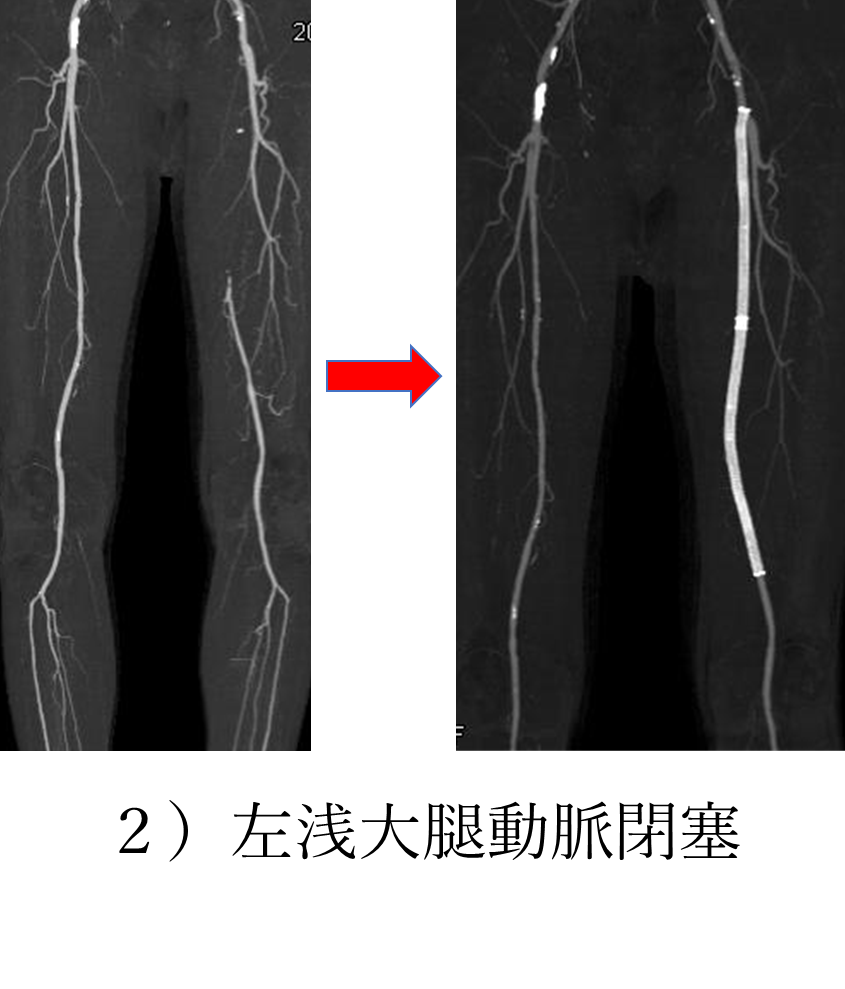

2)の左浅大腿動脈閉塞の方は、品川駅から当院まで徒歩で来られる際に柘榴坂(品川駅から当院までの間にある坂)を休み休みでないと上って来ることができないという間欠性跛行を訴え、当院で治療に至った患者様です。